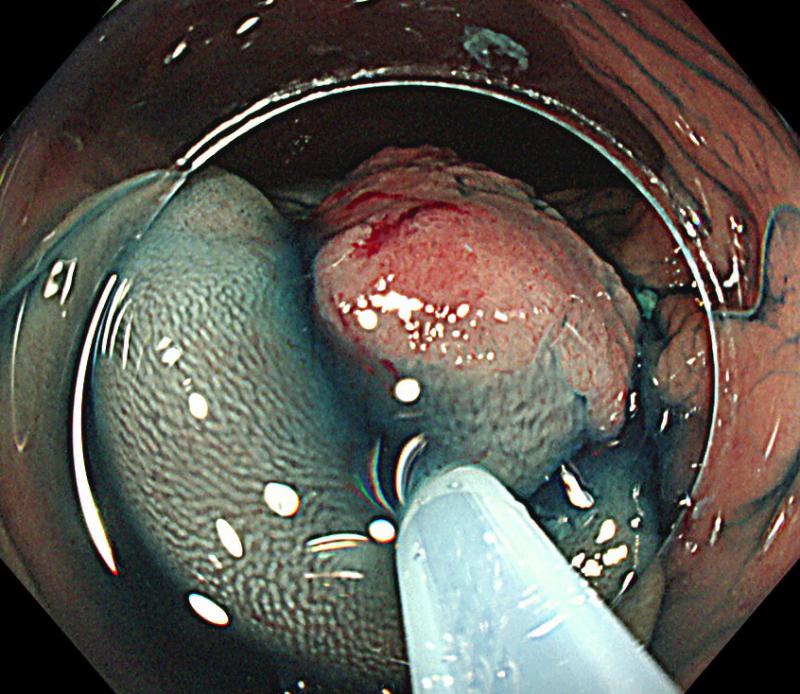

⑤大腸ESD

1:大腸に扁平隆起性病変を認めます。

2:デュアルナイフJで粘膜下層を剥離しています。

3:大腸癌切除後の潰瘍です。

4:切除後の大腸癌の標本です。